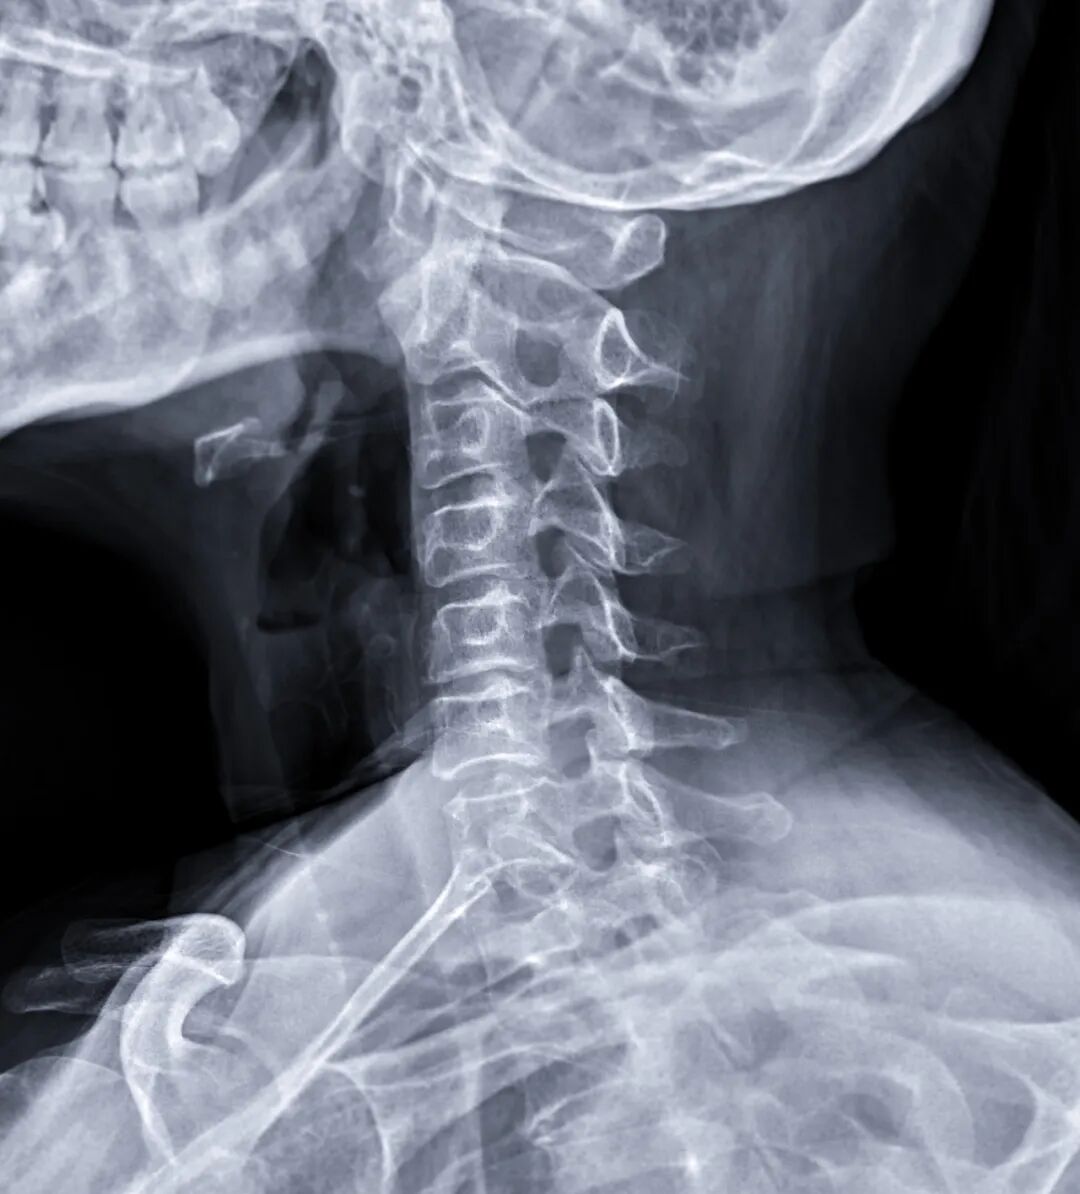

DR:最常用的“第一道检查”

你可以把它理解成“高级版X光”

📷利用X射线穿透人体,因为骨骼、肌肉、脂肪等组织密度不同,对X射线的吸收也不一样,就在底片或探测器上形成黑白影像。

它最适合看什么?

🔍骨折、关节脱位

🔍肺炎、肺结核等肺部问题

🔍脊柱形态、骨质增生

🔍体内金属异物、节育环位置

优点:速度快、辐射剂量低、价格亲民

· 它是二维图像,前后组织会重叠,有时候需要多角度拍摄。

· 检查前需去除拍摄部位的金属物品(如项链、带金属扣的内衣等),以免干扰影像。

· 孕妇或备孕女性务必提前告知医生,评估必要性并做好防护。